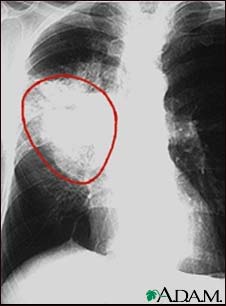

Lung cancer, frontal chest X-ray

A CXR in a patient with central cancer of the right lung. Notice the white mass in the middle portion of the right lung (seen on the left side of the picture).